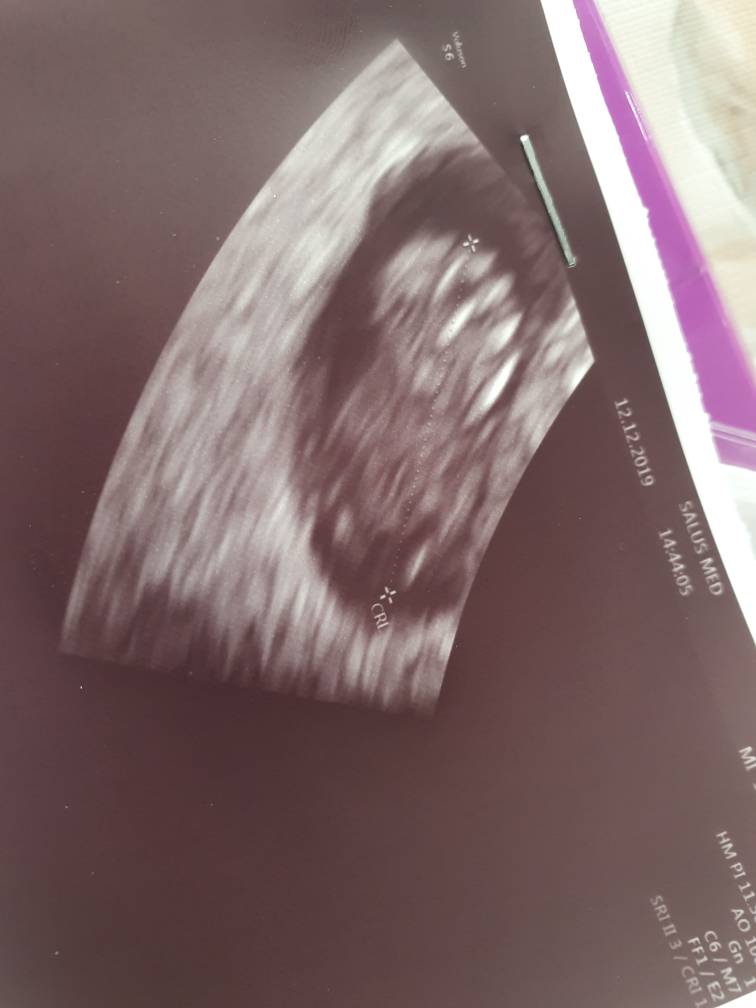

Dzien dobry dziewczyny. Ja wczoraj zaliczylam wizyte u mojego gin w zwiazku z bolami, jakie mialam od wtorku. Bolami,ktore przechodzily na kregoslup i uczuciem klucia. Byl zaskoczony ze sie pojawilam,bo bylismy umowieni na styczen. Ale zbadal, wysluchal i uznal ze to reakcja organizmu,bo przeciez od wtorku powinnam miec okres a nie fasolke i organizm potrzebuje jeszcze sie przestawic. Zaproponowal 6 tab.nospy i leniwy tryb zycia [emoji1787] na sam koniec pokazal dzidzie. Mowi ze serce ladnie bije, a ja mu na to,ze nic nie widze. Zatem ten ustawia sonde na spokojnie byl zobaczyla ruch serduszka i mowi do mnie "dlatego to ja robie usg" [emoji1787] Dodatkowo zapytany o badania prentalne powiedzial, ze bez wyjatku robi ale o nich porozmawiamy w styczniu.

A Wam Ciotki przedstawiam 1.75cm szczescia [emoji173]Zobacz załącznik 1056276